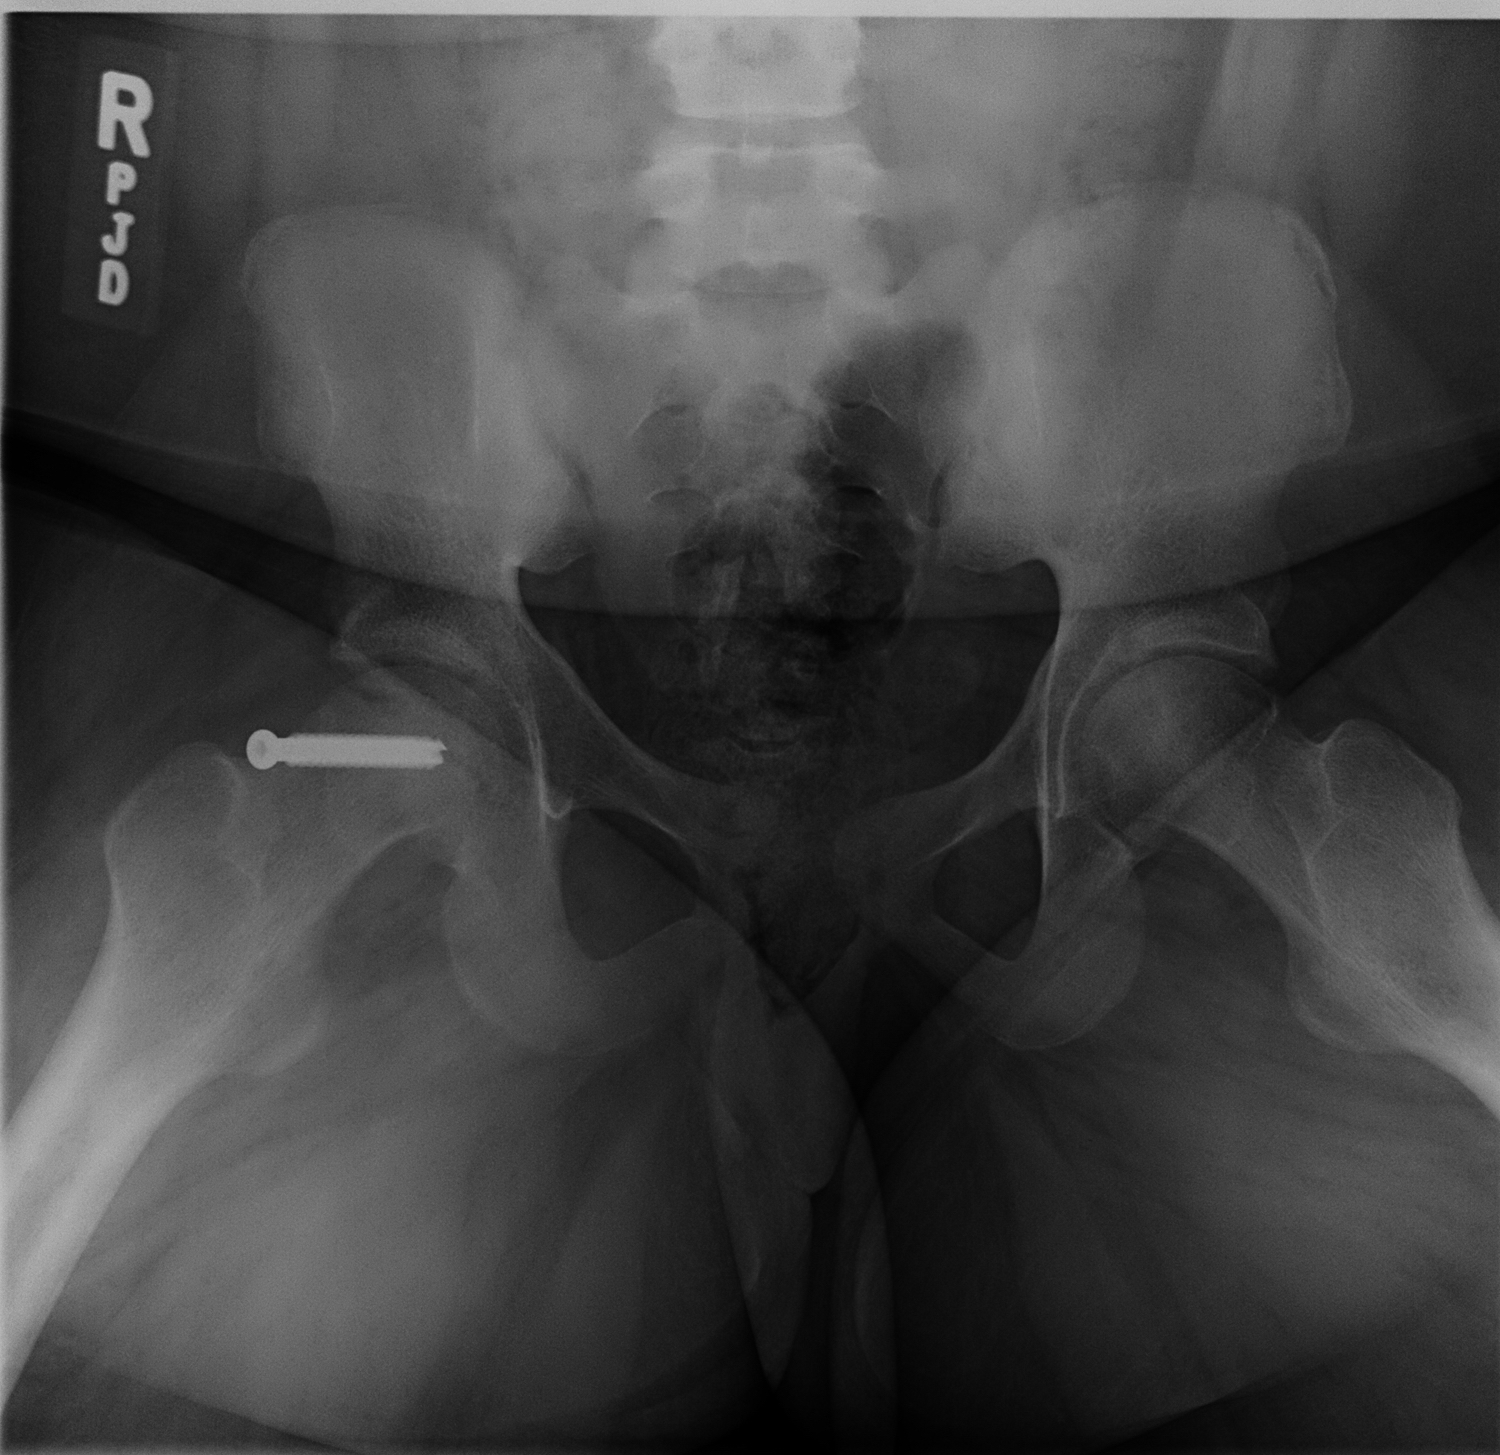

She was admitted directly to the hospital on strict bed rest and later underwent in situ screw fixation of her right SCFE (Figure 2). She was instructed to remain non-weight-bearing on her right leg using crutches for 6 weeks.